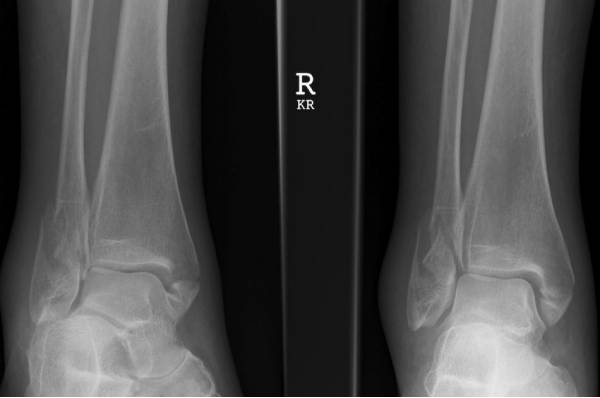

Maisonneuve骨折

由外旋暴力导致的腓骨近端骨折, 常常合并下胫腓分离、内踝骨折、三角韧带撕裂、前距腓韧带断裂、骨间韧带损伤、下胫腓韧带撕裂、后踝骨折等损伤,属于旋前-外旋三度损伤,踝关节不稳定。